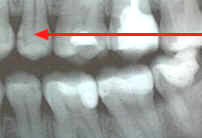

La técnica tiene ventajas

con respecto a la radiografía periapical, debido que

reduce el tiempo de exposición a la radiación y disminuye

los costos y honorarios.

Técnica:

La cabeza del paciente se

coloca de manera que el plano de oclusión quede paralelo al del

piso. El rayo central se dirige al punto de contacto de los

dientes superiores con los dientes inferiores y paralelo a sus

superficies proximales, con el tubo formando un ángulo de 5 a

10º por encima del plano horizontal.

Ver figura 5. Para los dientes posteriores es

deseable tomar dos vistas de cada lado:

-

una en la que la película

se coloca más atrás para incluir el espacio inter-proximal

entre el segundo y el tercer molar,

y la otra lo bastante adelante

como para tomar la cara distal del canino. Solo necesita cuatro

películas para el diagnóstico de caries en todos los sectores

posteriores.

Cuando el tercer molar se

encuentra en proceso de erupción y se observa solo una parte de la

corona clínica a la inspección visual, es de utilidad diagnóstica

general, una imagen de una radiografía periapical de esa pieza

dental en particular.

Figura 5 |